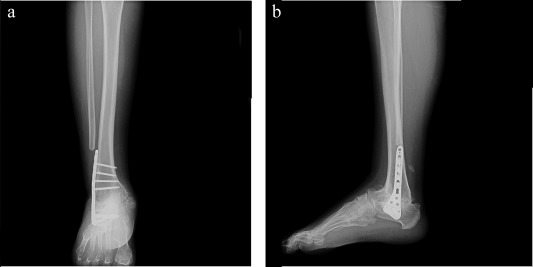

A short leg non-weight-bearing cast was applied postoperatively for 8–12 weeks. After cast removal, gradual weight-bearing was allowed with solid ankle foot orthoses until solid healing was observed. Full weight-bearing was permitted when solid fusion was achieved according to clinical and radiological examination. At 6 weeks, 3 months, 6 months, and 1 year postoperatively, X-rays were obtained to evaluate ankle fusion (Fig. 1  ;  Fig. 2 a, b).

(a and b). Postoperative anteroposterior and lateral views at 6-month follow-up.

Fig. 2.